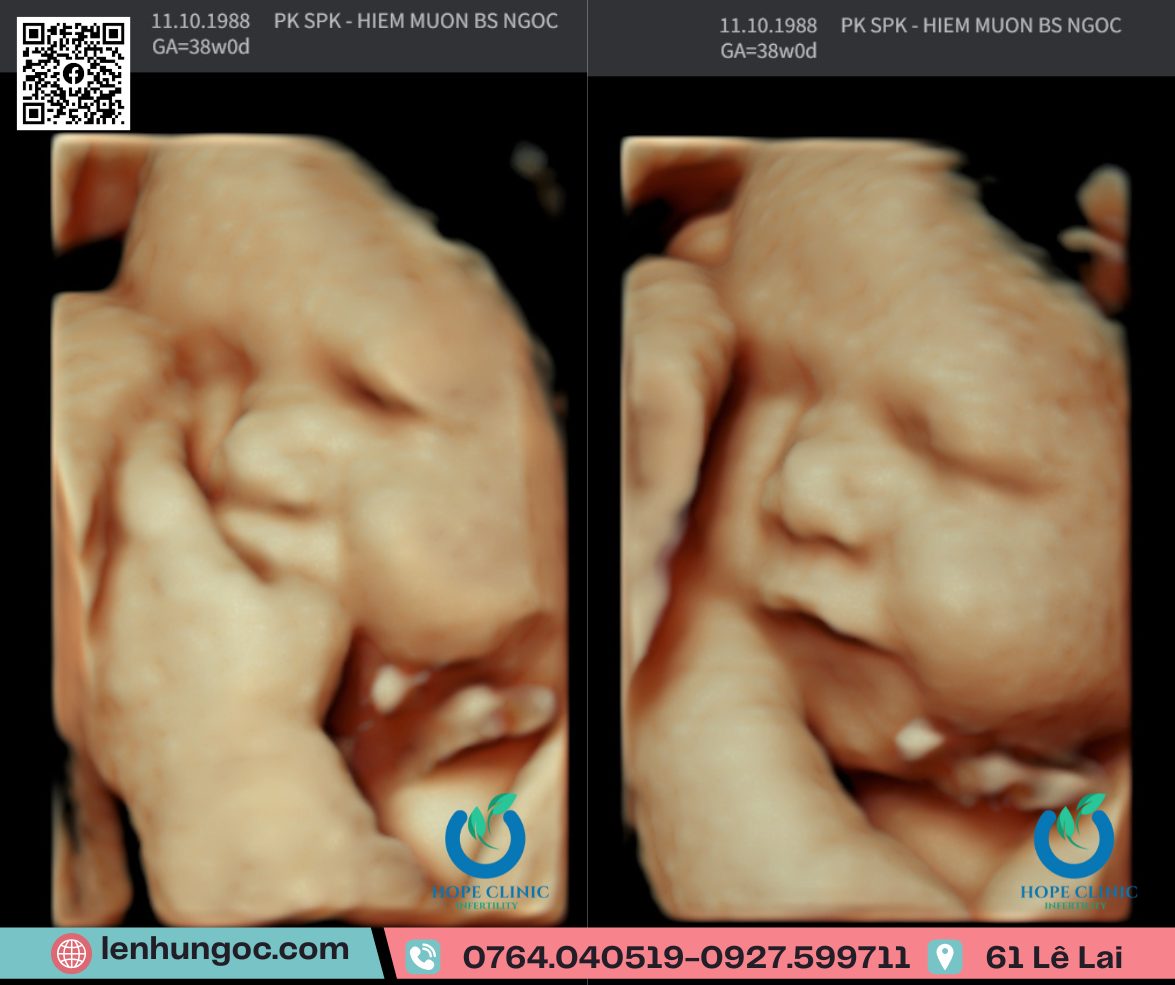

• Siêu âm thai 5D-6D cho hình ảnh rõ nét, chẩn đoán chính xác.

Phòng khám hướng đến mục tiêu đồng hành cùng mẹ bầu để mỗi buổi khám thai là một hành trình an tâm và hạnh phúc. 📍 Địa chỉ: 61 Lê Lai – Tp. Đà Nẵng 📞 Zalo tư vấn : 0764.040519 – 0927.599711 🌐 lenhungoc.com Mỗi buổi khám thai, không chỉ để đánh giá tình trạng mẹ và thai mà còn là cơ hội để bố mẹ nhìn ngắm em bé của mình lớn lên từng ngày trong bụng mẹ. Hiểu được điều đó, phòng khám luôn cố gắng gởi đến bố mẹ hình ảnh con yêu rõ nét nhất, từ khuôn mặt, chiếc mũi, khoé miệng, những ngón tay ngón chân bé tí,…